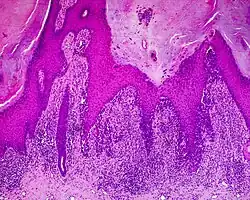

Zaawansowany czerniak szerzący się powierzchownie (widoczny wzrost pionowy zmiany)

Obraz histopatologiczny czerniaka szerzącego się powierzchownie

Czerniak szerzący się powierzchownie

Jest to najczęstszy podtyp czerniaka stanowiący około 70% wszystkich przypadków tego nowotworu[81][82]. Charakteryzuje się promienistym i powierzchownym rozprzestrzenianiem się guza początkowo w naskórku, a w późniejszym etapie w warstwie brodawkowej i siateczkowej skóry właściwej. Czerniak szerzący się powierzchownie może pojawiać się w dowolnej lokalizacji, szczególnie w miejscach wystawionych na intensywną, przerywaną ekspozycję na promieniowanie ultrafioletowe. U kobiet zwykle występuje na kończynach, a u mężczyzn w obrębie tułowia[83].

Makroskopowo jest płaską lub płasko-wyniosłą zmianą z typową asymetrią jej budowy. Zmiana zwykle jest ostro ograniczona, a granica zmiany jest nieregularna, pokarbowana, może przypominać mapę[81][84]. Rzadziej granica jest nieostra[81]. Wykwit jest nierównomiernie zabarwiony, przybiera kolor od ciemnobrązowego do ciemnoczarnego. Szare i białe obszary wskazują na regresję. Czerwone obszary odpowiadają zapaleniu lub wzmożonemu unaczynieniu guza[81]. Możliwe jest występowanie bezbarwnych zmian, które przypominają chorobę Bowena lub Pageta[81].

W bardziej zaawansowanych stadiach czerniak szerzący się powierzchownie może osiągać znaczną średnicę i zmienia wzór wzrostu z horyzontalnego na pionowy, co klinicznie ujawnia się jako uniesienie zmiany. Powstają guzki łatwo ulegające erozji, owrzodzeniu i krwawiące. Możliwa jest obecność zmian satelitarnych[81].

Mikroskopowo czerniak szerzący się powierzchownie początkowo rozprzestrzenia się horyzontalnie (pagetoidalnie), głównie w naskórku powyżej połączenia skórno-naskórkowego, gdzie obecne są atypowe melanocyty. Nowotwór w późniejszym etapie wzrostu poziomego w wyniku nacieku również jest obecny w skórze właściwej w warstwie brodawkowatej i siateczkowatej. W czasie wzrostu poziomego w naskórku czerniak nie daje przerzutów i nie wykazuje oznak angiogenezy. Następnie dochodzi do wzrostu pionowego guza i nowotwór wrasta w głębsze warstwy skóry i zajmuje warstwy brodawkowatą i siateczkowatą[85][83].

Atypowe melanocyty są większe, mogą być wielokątnego lub owalnego kształtu, komórki zawierają obfitą ilość cytoplazmy, jądra posiadają nieregularnie grudkowaną chromatynę i cienką błonę jądrową[86][81]. Melanocyty występują pojedynczo lub w gniazdach[81]. Dystrybucja i kształt gniazd jest nieregularny, gniazda charakterystyczne dla czerniaka są duże i mają słabe odgraniczenie[86]. Gniazda mogą ulegać zlewaniu[86][81]. W czerniaku in situ reakcja zapalna jest mało nasilona lub nieobecna[81]. Widać liczne mitozy, figury mitotyczne mogą nie występować[86].

W fazie pionowego wzrostu występują obszerne i bardzo nieregularne gniazda atypowych melanocytów, które mogą znajdować się w znacznej odległości od siebie albo łączyć się. Warstwa naskórka jest nierównomiernie scieńczała, dochodzi do zajęcia przydatków skóry[86]. Komórki tracą cechy dojrzewania[81][85]. Mogą być obecne komórki, które uległy martwicy[86]. Obecny bywa naciek limfocytów[81].

Czerniak może ulegać częściowej lub (znacznie rzadziej) całkowitej regresji, co może być powodem trudności diagnostycznych ze znalezieniem guza pierwotnego. W części guza, która uległa regresji, ilość melanocytów jest znacznie zmniejszona w stosunku do pozostałej części zmiany. Dochodzi do zwłóknienia w warstwie brodawkowej, proliferacji naczyń i ich poszerzenia oraz różnego stopnia nacieku limfocytów i melanofagów[81].